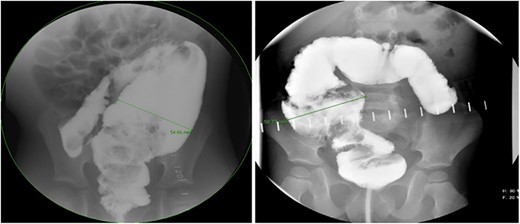

There is a subset of patients in whom primary transanal pull-through in those >2 years of age at the time of surgery is possible. While a previous case series reported that 18.8% of their late-diagnosed HD patients underwent transanal primary pull-through, these authors did not describe outcomes or reasons for choosing the operative approach [7]. In case series, the characteristics of patients who were able to undergo primary transanal-only pull-through include overall earlier age (2–6 years) vs. those diagnosed later. On contrast enema, they exhibited a limited degree of megacolon (Figs 1 and 2). Proximal colonic dilation was absent in all four patients that we felt were good candidates for a transanal-only approach. However, proximal colonic dilation (proximal of the sigmoid) was visualized in 15 patients, and therefore, a transanal-only approach was not offered. The ability to identify a clear transition zone low in the rectosigmoid was also observed in each patient. Finally, the ability to empty the colon preoperatively whether through laxatives or rectal irrigations was also present.

Representative contrast enema study. Note the lack of dilated proximal colon and defined transition zone in the low rectosigmoid colon. (Candidate for transanal only).

Prior to beginning the pull-through, the colon should be irrigated to make sure that any retained fecal matter has been cleared. Careful assessment of the transition zone and confirmation of minimal proximal colonic dilatation allows for prone-only positioning and a transanal-only approach (Fig. 1). The Lone Star retractor and full-thickness dissection begin 1.0 cm proximal to the dentate line in the Swenson plane. Biopsies should be taken in a single line so as not to lose orientation [8] and 10–15 cm past the positive biopsy for ganglion cells to assure that normal caliber colon is reached before performing the anastomosis. Challenges with the transanal-only approach occur when there is a large amount of proximal colonic dilation, and therefore, in this instance, we recommend a laparoscopic approach for intraoperative mobilization of the descending and proximal colonic mobilization off the left retroperitoneum [9]. If at the time of anastomosis of the dilated ganglionated bowel, anal caliber size discrepancy is encountered a trick can be employed by placing four quadrant sutures and then bisecting each quadrant again and again with interrupted sutures [10].